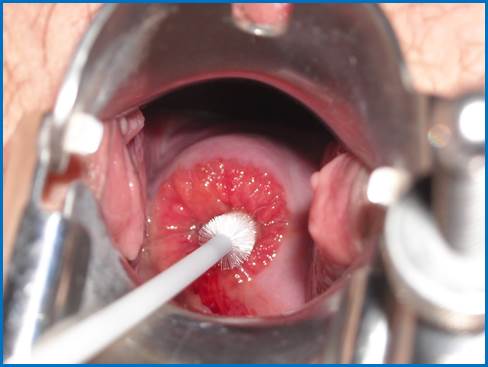

Фото. Забір матеріалу для скринінгу на рак шийки матки

(цитологічне дослідження) проводиться із піхвової частини шийки матки шпателем Ейра, з цервікального каналу – гінекологічною щіточкою. Ілюстрації beautifulcervix.com.